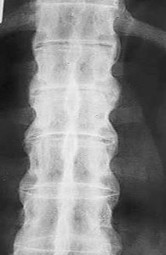

A 16-year-old male is brought to the clinic by his mother, who is concerned about his "round back." He complains of dull mid-back pain after standing for long periods. Standing lateral radiographs reveal a thoracic kyphosis of 65 degrees.

According to the Sorensen criteria, what specific radiographic finding is required to confirm the diagnosis of classic Scheuermann's disease?

Explanation